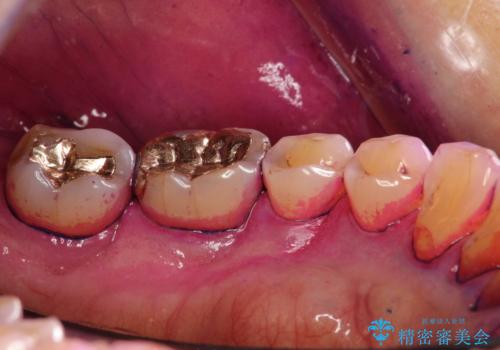

- 2カ月ごとにメンテナンスにいらしている方です。染め出しをしての歯磨きチェックとPMTC30分コースを行いました。

染め出し液を使ってプラークを染め出すことにより、普段の歯みがきで磨き残している場所を目で確かめることができます。